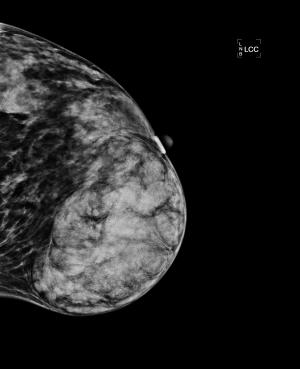

37-year-old female with no significant family history of malignancy presents with asymmetric enlargement of the left breast, palpable on physical examination.